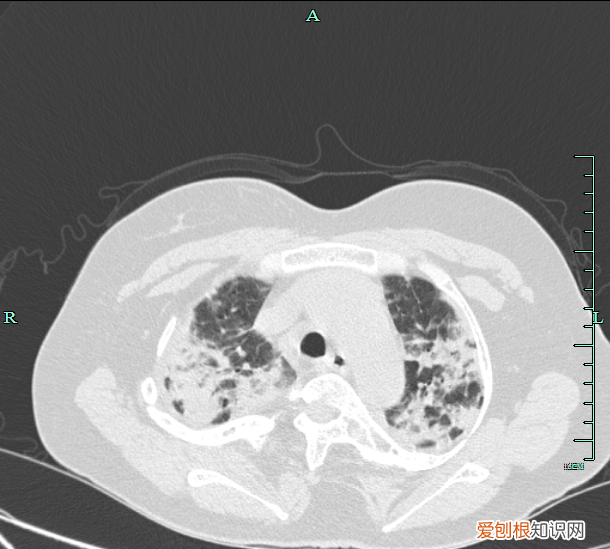

文章插图

治疗前胸部CT可及双肺斑片状密度增高影